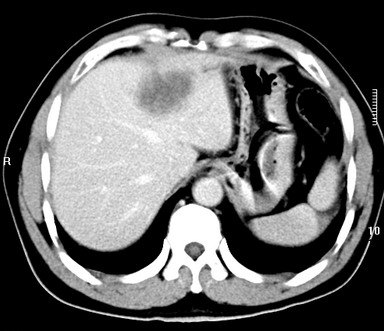

标题: CT19720:肝右叶血管瘤。肝左叶内侧段病灶考虑什么? [打印本页]

标题: CT19720:肝右叶血管瘤。肝左叶内侧段病灶考虑什么?

男,48岁,肝区不适月余,伴隐痛。

支持右叶血管瘤,左叶病灶考虑肝腺瘤。

1)不排除肝左叶肝癌。2)肝右叶血管瘤。

肝左叶炎性病变,肝癌待排。2)肝右叶血管瘤。

1.肝右叶血管瘤;2.肝左叶炎性假瘤?肝癌?建议穿刺活检.

右叶病灶典型,左叶病变慢性炎块

1、肝右叶血管瘤(典型)。

2、肝左叶病灶,强化不明显,疑炎性假瘤,建议结合临床并密切随访。

1、肝左叶炎性病变,肝癌待排。

2、肝右叶血管瘤。

肝左叶脓肿,肝癌待排。2)肝右叶血管瘤